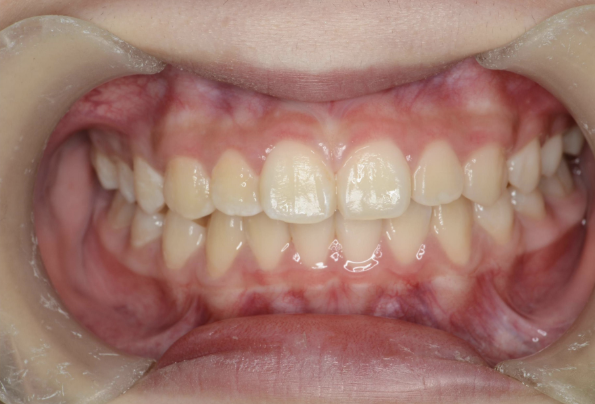

お子さんが「矯正治療」をはじめる時に直面する問題は 「装置が目立つ」、 そして「歯を抜く」ことがあげられます。

10歳を超えてからの治療開始ではそのようにならざるを得ないことが多いのです。

しかしながら、5〜7歳頃に治療をスタートすれば 目立ちにくい装置で、歯を抜かずに治療できることがあります。

10歳を過ぎてからの矯正治療の場合、大人の歯を抜いて治療することが多くなります。 一方、下の前歯が生えてくる5〜7歳頃から治療を始めると、大人の歯を抜かずに治療することが可能です。 抜かずに治療するには早期に治療を開始することが大切です。

矯正治療でよく使われるはり金の装置は目立ってしまいます。 当院では、こども専用の取り外し式のマウスピース型装置を用います。 装置を使うのはご自宅で起きている時の1時間と夜寝ている時です。 学校につけていく必要が無いので、周りの人に気づかれずに治療を進められます。

歯並びが悪いのは、あごの骨が成長不足で小さいことで起こります。 当院で行なっているこどもの歯ならび治療はあごの骨に働きかけることができます。 骨に働きかけることで成長不足のお子さんの骨が成長して、顔つきが良い方向に変わっていく可能性があります。 実は大きくなってからの矯正治療は歯が並んでいるだけで骨やお顔つきは変わっていないのです。 5〜7歳ぐらいで治療を開始すると成長不足の骨に働きかけて、より良い顔つきになれる可能性があります。

※治療結果には個人差があります。